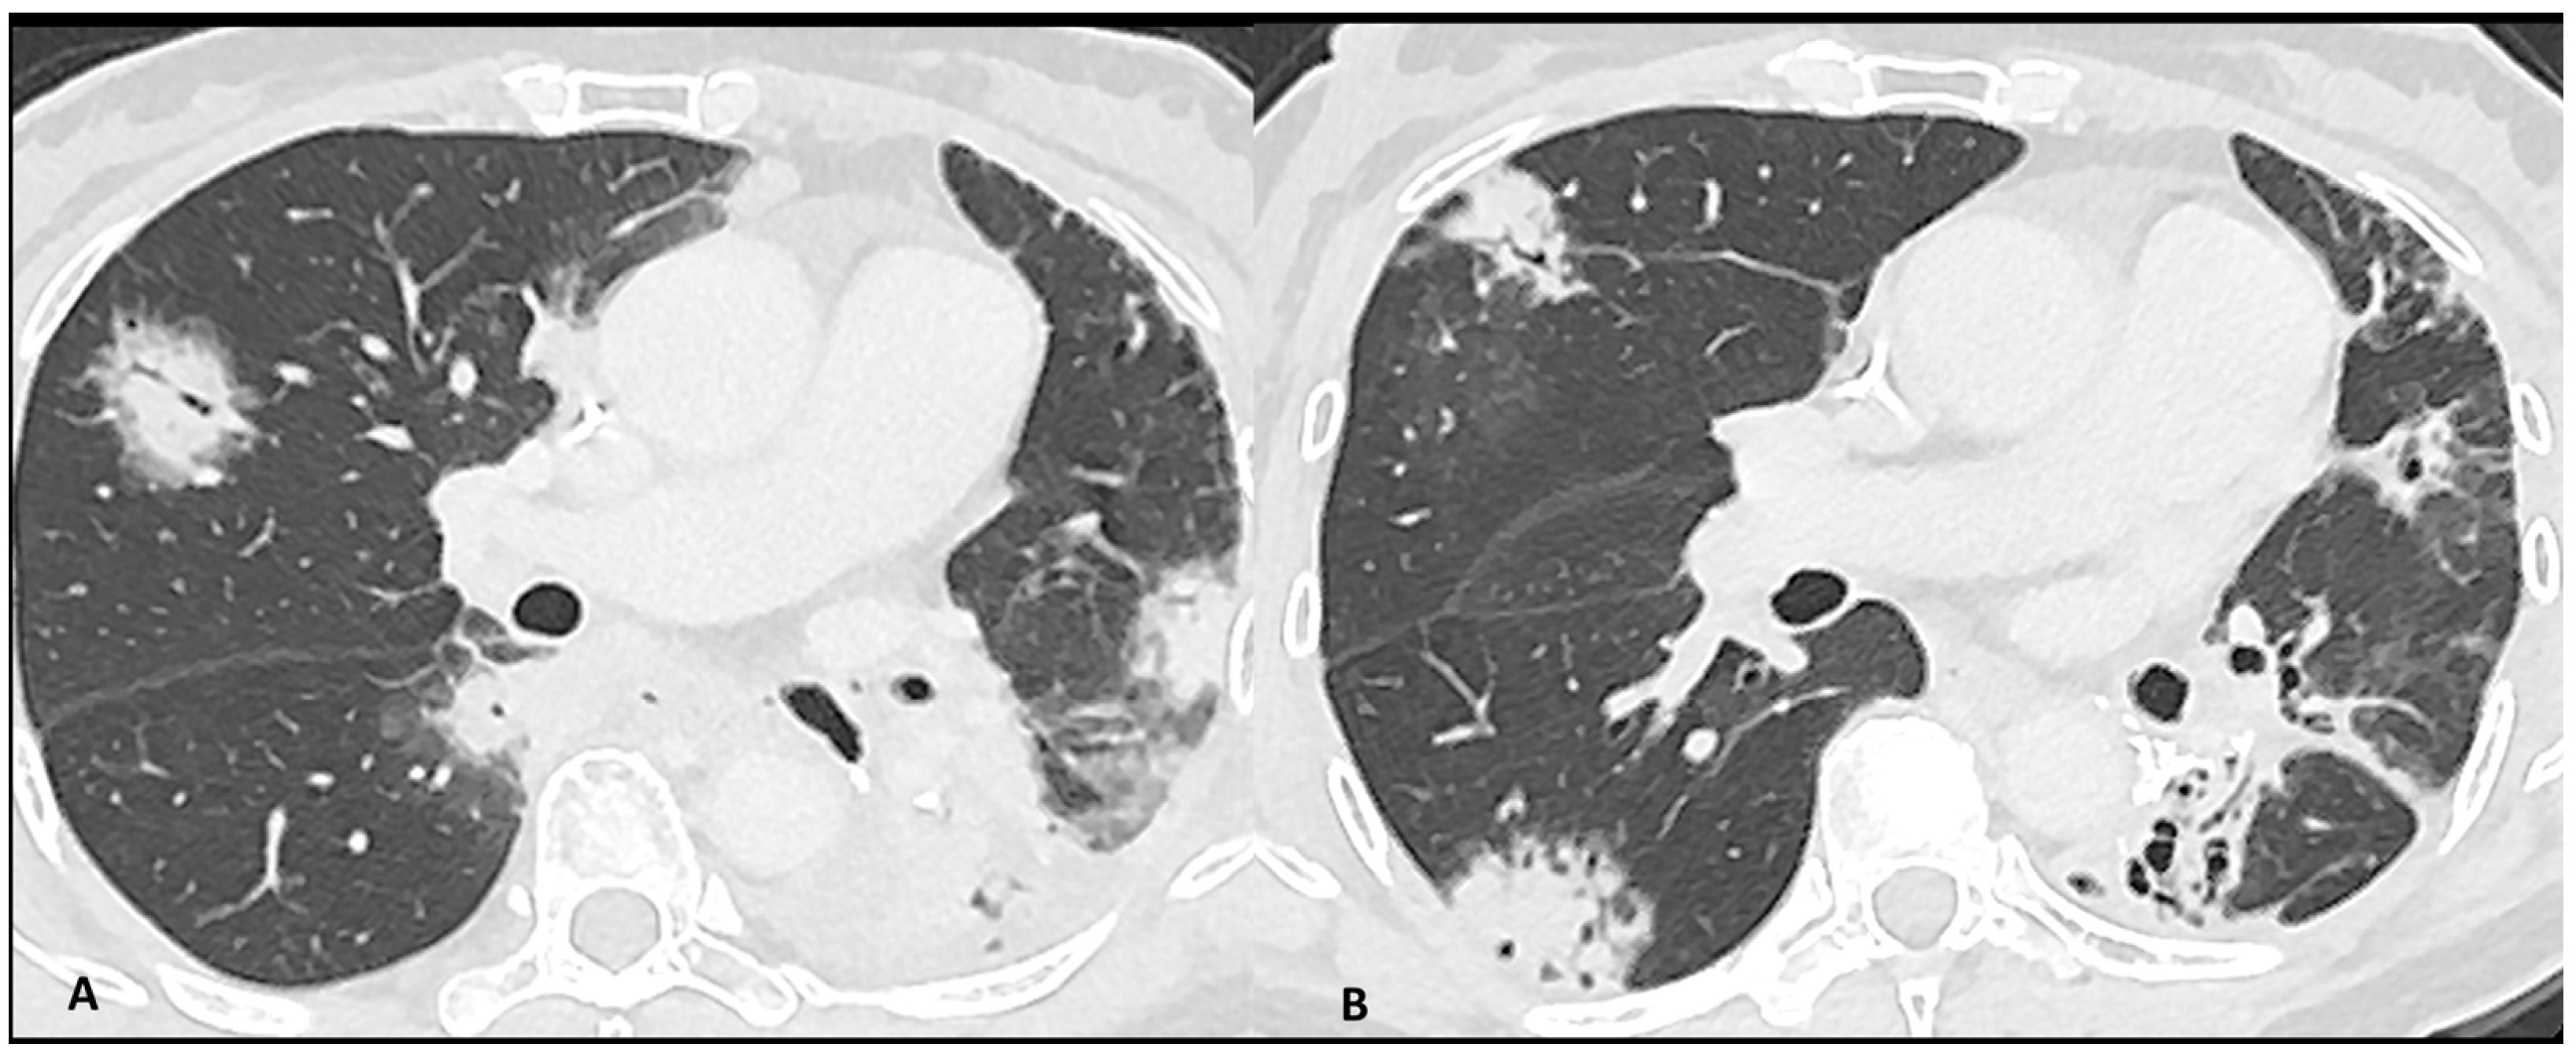

Imaging plays a major role in the identification, characterization, and follow-up of pulmonary irAEs. Chest X-ray is not recommended due to its limited sensitivity and specificity in detecting ICI pulmonary abnormalities [23]. Chest CT is the preferred imaging modality for suspected ir-pneumonitis with common radiological patterns including organizing pneumonia (OP), simple pulmonary eosinophilia (SPE), hypersensitivity pneumonitis (HP), nonspecific interstitial pneumonia (NSIP), and acute interstitial pneumonitis/diffuse alveolar damage (AIP/DAD) [23,25,39]. Organizing pneumonia is the most frequent pattern and it is generally marked by peribronchovascular or subpleural consolidations or patchy ground-glass opacities, which often migrate over subsequent scans (Figure 2). Interestingly, the “halo sign”, a typical OP feature characterized by ground-glass opacity with a peripheral rim of consolidation, is uncommon in ir-pneumonitis. The extent of the lung involvement correlates with the severity of pneumonitis. A simple pulmonary eosinophilia pattern is usually detected in asymptomatic patients and presents as transient and migratory ground-glass opacities or nodules that may regress spontaneously (Figure 3). Nonspecific interstitial pneumonia typically shows bilateral and symmetrical peripheral ground-glass opacities with lower lobe predominance, which may be associated with reticulations and traction bronchiectasis, while hypersensitivity pneumonitis manifests as centrilobular nodules and lobular hypoattenuations representing small-airway disease. Acute interstitial pneumonitis/diffuse alveolar damage pattern is generally reported in most severe cases and it is characterized by extensive bilateral ground-glass opacities and dependent alveolar consolidations with bronchiectasis appearing in subsequent scans. Micronodules in three-in-bud distribution resembling infectious bronchiolitis as well as a single nodular or mass-like appearance mimicking malignancy have also been described [23,39,40]. Contrast injection is not required; however, it might be performed in routine cancer restaging or in suspected complications such as pulmonary embolism.

Figure 2.

Immuno-related pneumonitis with typical organizing pneumonia features in a patient developed after four cycles of antiPD-1 treatment for lung cancer. The images at the pulmonary trunk depict (A) multiple bilateral peribronchovascular consolidations lobe as well as an extensive lower lobe consolidation. A 4-week CT follow-up shows the regression of the previous consolidation but the appearance of new ones (B), representing the “migratory” aspect of the organizing pneumonia.

Figure 3.

Immuno-related pneumonitis with simple pulmonary eosinophilia pattern pathologically confirmed in a patient with metastatic esophageal cancer receiving chemotherapy and antiPD-1 treatment. The follow-up scans show multiple “migratory” patchy ground-glass opacities in the upper right lobe (arrow).

Distinguishing between ir-pneumonitis, infection, and tumor progression at imaging may be not straightforward as they often share similar radiological features (Figure 4) [23]. Ir-pneumonitis not only may present as nodular or consolidative lesions mimicking malignancy but it also frequently affects the regions where primary lung cancer and/or lung metastases are located, misleading tumor progression or recurrence [41]. Another challenge in differential diagnosis occurs in case of new-onset lung abnormalities in the radiotherapy field as radiation pneumonitis typically presents with an organizing pneumonia pattern and can manifest even beyond 12 weeks post-radiotherapy due to “radiation recall” phenomena triggered by ICIs [23,41]. Although ir-pneumonitis is primarily located in the radiotherapy field, unlike radiation pneumonitis, it often extends beyond it [41,42]. An additional important challenge for oncologists is identifying the specific drug responsible for pulmonary toxicity in patients receiving ICI in combination with other treatments in particular with molecular targeting therapy such as EGFR TKI, antiangiogenic TKIs, and vascular endothelial growth factor receptor (VEGF) inhibitors [36]. In fact, since they share similar patterns, the identification of the responsible drug is often challenging. The timing of drug introduction and the awareness of the typical features associated with different treatments may aid in identifying the implicated drug and discontinuing it [39,43].

Figure 4.

Mimicker of immune-related pneumonitis: tumor progression in a patient with unresectable stage III receiving consolidation immunotherapy after chemoradiotherapy. At baseline CT (A) the peri-hilar lesion appearance after radiation therapy is seen (arrow). The restaging CT four months after the introduction of antiPD-1 (B) shows the appearance of an extended ground-glass opacity (arrowhead) and septal thickening in the left lower lobe as well as the increase in the size of the peri-hilar mass (arrow) and a semi-circumferential pleural effusion (star), findings suspicious for tumor progression with lymphangitic involvement rather that immune-related or radiation-related pneumonia. The intense uptake of the peri-hilar lesions at PET/CT (C) confirms the tumor progression.